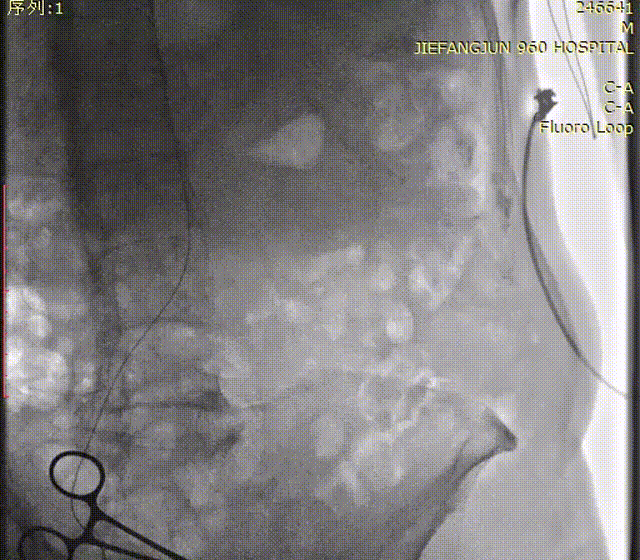

瓣膜释放后造影

术后入路检查

术后造影提示,瓣膜位置、膨胀形态良好,主动脉瓣狭窄解除,几乎无瓣周漏和反流,入路血管未见渗血,手术圆满结束。